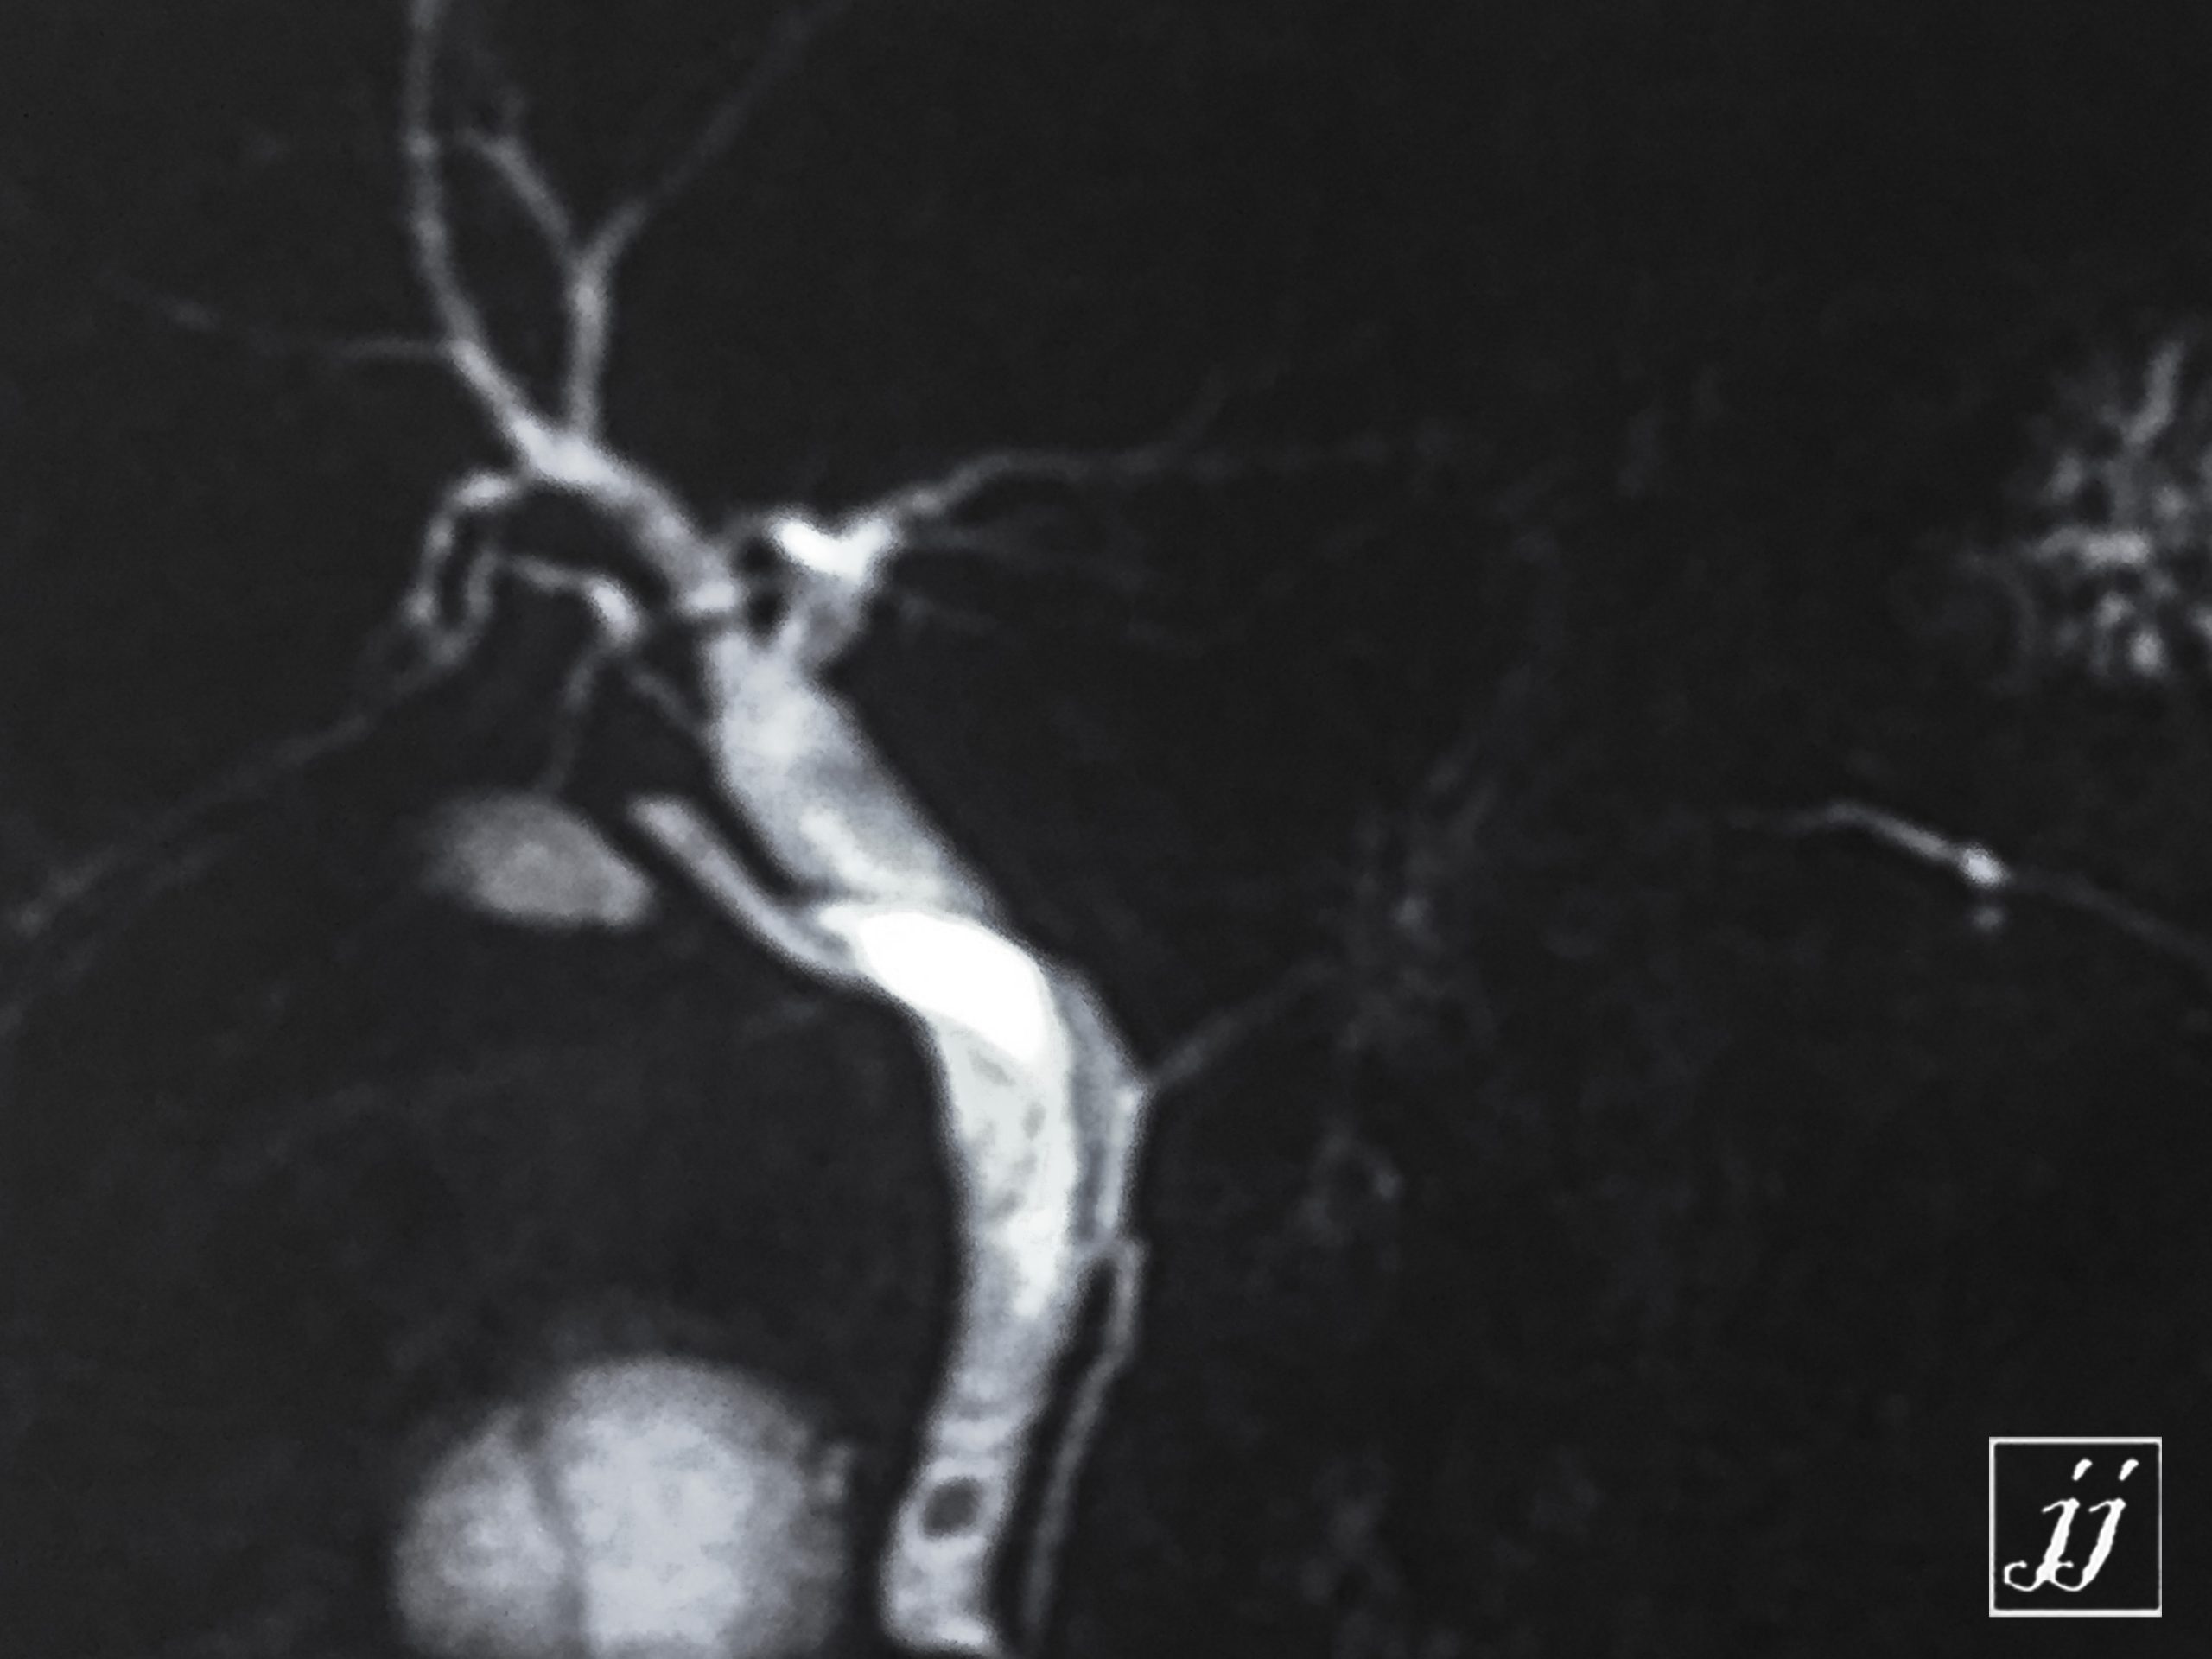

Abdomen- Normal MRCP with stone distal CBD a large right kidney cyst (4)